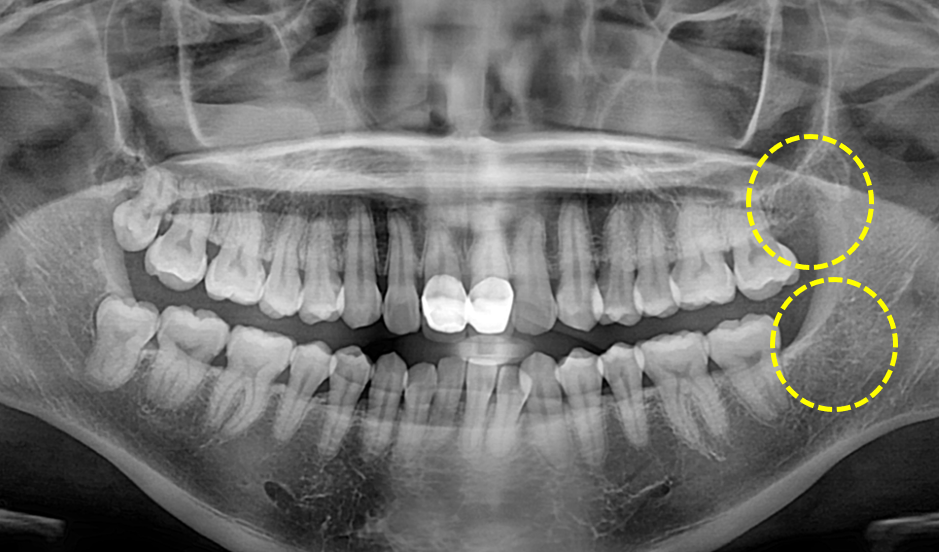

상, 하악 사랑니 발치

After

발치 후 6개월 이상 지나게 되면 발치와가 치조골로 치유된 모습을 확인하실 수 있습니다.

위 케이스는 발치와가 완벽히 치유되어 그 전에 치아가 있었는지 조차 잘 모를 정도가 되었습니다.